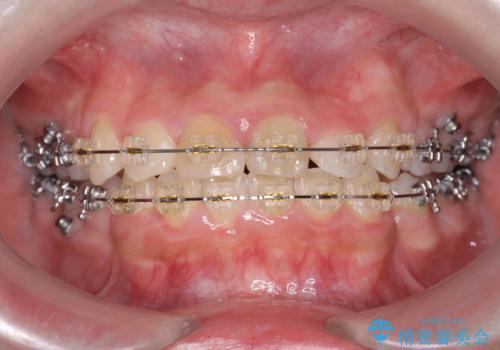

- プラスチック装置

- 治療期間

- 2年6ヶ月

- 治療回数

- 10-30回

神経の治療を先に行い、ワイヤー矯正を行いました。

上下の小臼歯を抜歯しています。